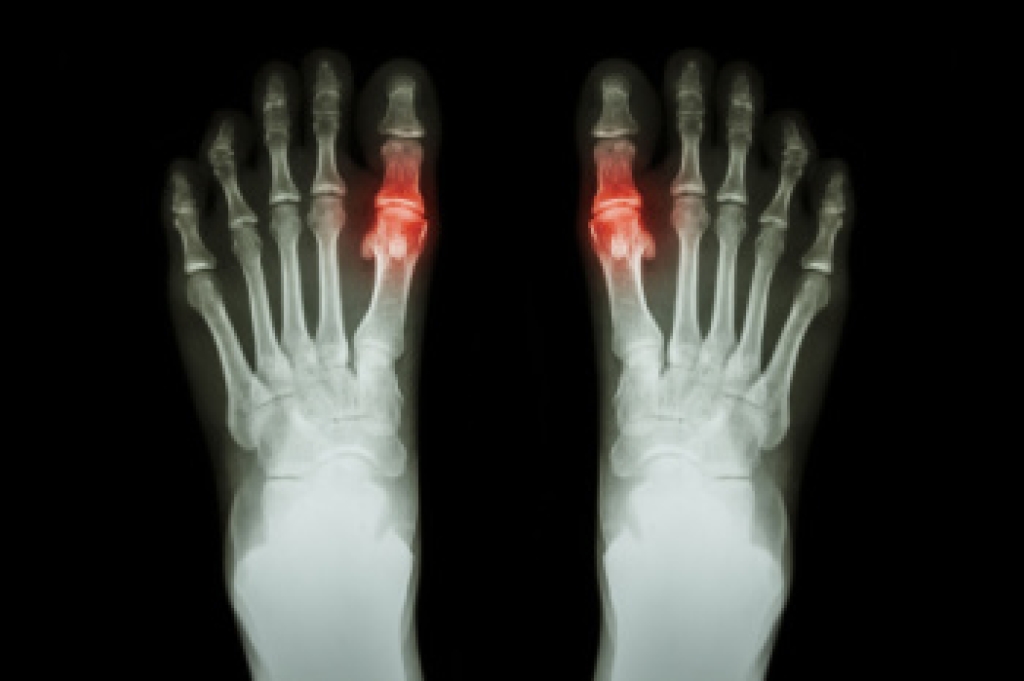

Gout is a form of arthritis caused by the buildup of uric acid crystals in the joints. This buildup occurs when the body produces too much uric acid or cannot effectively eliminate it. Risk factors for developing gout include a diet high in red meat and seafood, excessive alcohol consumption, and obesity. Certain medical conditions such as hypertension and diabetes also increase the likelihood of developing gout. Symptoms of gout often appear suddenly and include intense joint pain, redness, and swelling, typically in the big toe. The affected joint may feel warm and extremely tender to the touch. Gout attacks can be recurrent, leading to chronic pain and joint damage if left untreated. The pain from gout can be debilitating. If you have developed this condition, it is suggested that you consult a podiatrist who can offer you relief and prevention methods.

Gout is a form of arthritis that is characterized by sudden, severe attacks of pain, redness, and tenderness in the joints. The condition usually affects the joint at the base of the big toe. A gout attack can occur at any random time, such as the middle of the night while you are asleep.